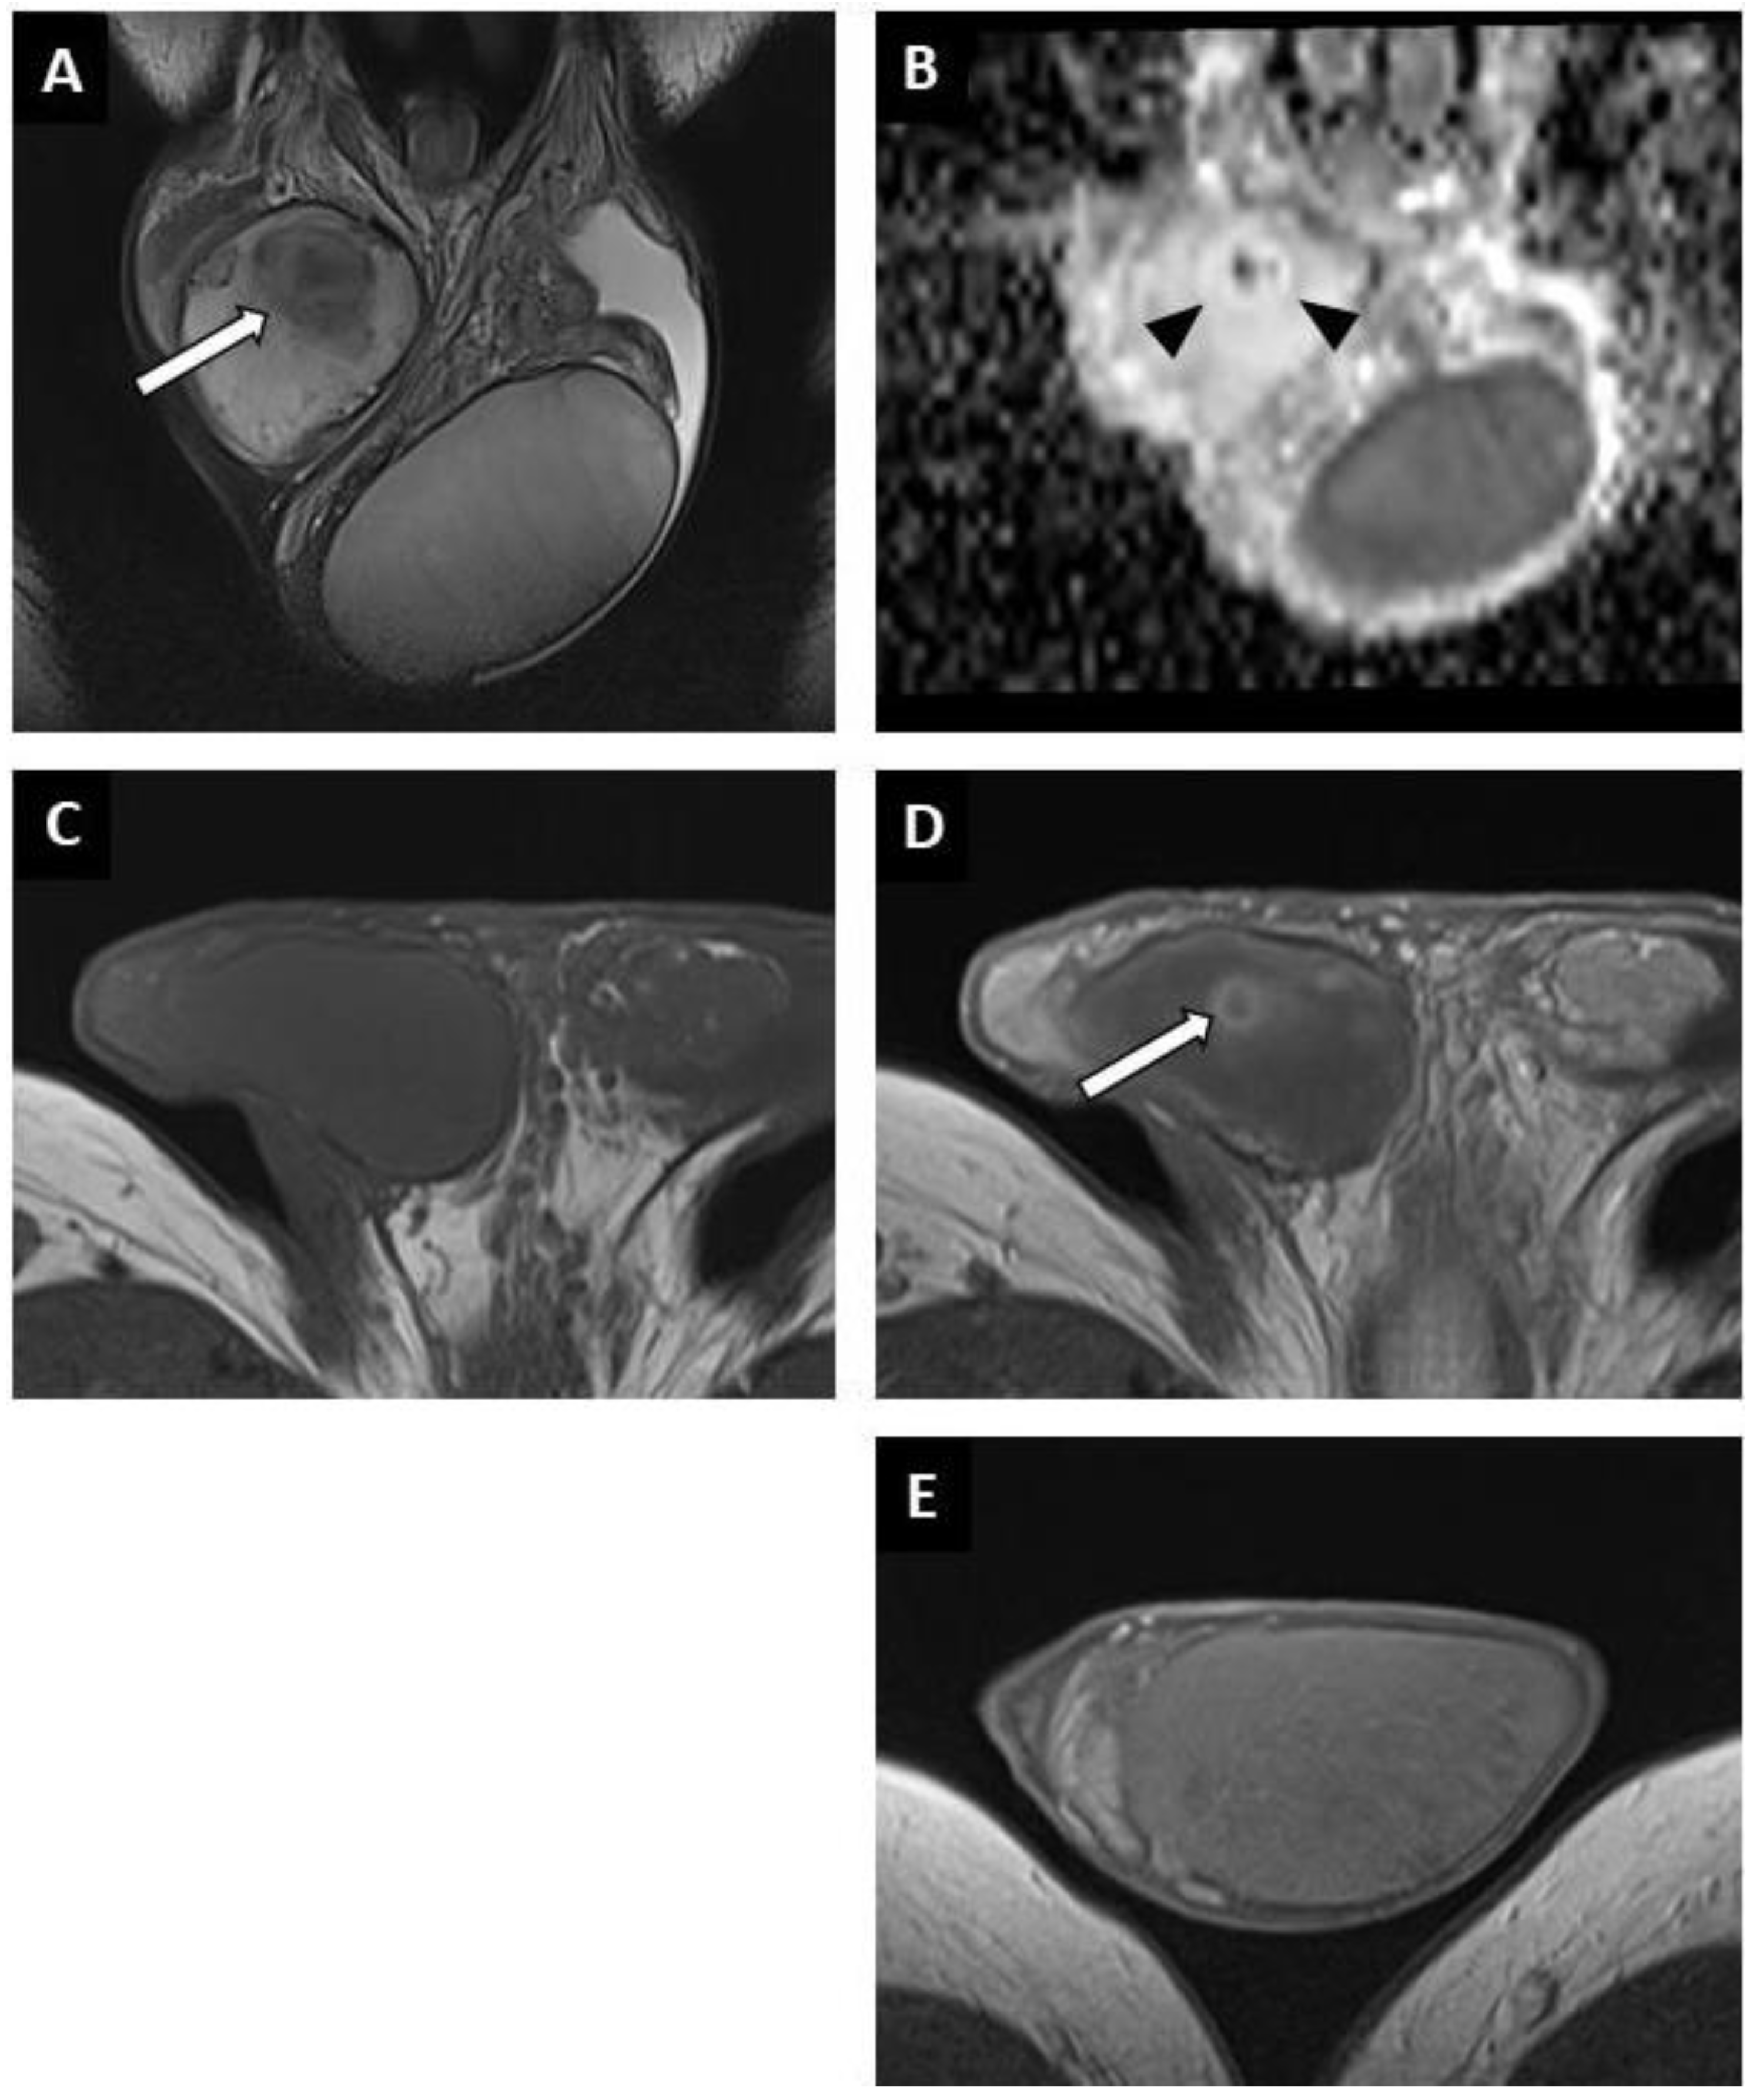

3.2.1. Conventional US Findings

3.2.2. MRI Findings

| Lesion shape (T2WI) | ||||

| - Round or oval nodule | 18 (81.8) | 8 (80) | 9 (100) | 34 (82.9) |

| - Non-nodular area | 4 (18.2) | 2 (20) | 0 | 7 (17.1) |

| Lesion signal | ||||

| - Hyposignal on T2WI | 22 (100) | 10 (100) | 9 (100) | 41 (100) |

| - Hyposignal on DWI | 17 (77.3) | 10 | 0 | 32 |

| - Hyposignal with focal hypersignal spot on DWI | 5 (22.7) | 0 | 0 | 5 (12.2) |

| DCE T1WI | ||||

| - Reduced enhancement matching to lesion | 3 (13.6) | 3 (30) | 3 (33.3) | 9 (22) |

| - Reduced enhancement overlapping the lesion | 13 (59.1) | 7 (70) | 6 (66.7) | 26 (63.4) |

| - Reduced enhancement overlapping the lesion with focal early and strongly enhanced nodule | 5 (22.7) | 0 | 0 | 5 (12.2) |

| - Reduced enhancement matching to lesion with peripheral ill-delineated area of increased enhancement | 1 (4.5) | 0 | 0 | 1 (2.4) |